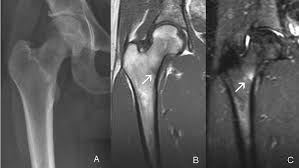

If an x-ray or MRI at the sports clinic confirms that youre experiencing a stress fracture in the hip the doctor will likely instruct you to rest. There are different operations which are. This depends on the fracture site and whether it is a simple crack or a displaced fracture.

Medications for Stress Fractures You can take over-the-counter medications to manage pain. Initial treatment of a hip stress fracture may include X-rays a magnetic resonance imaging MRI scan or a bone scan to further evaluate your condition.

Coronal Mri T1w Image Showing The Stress Fracture As Linear Download Scientific Diagram